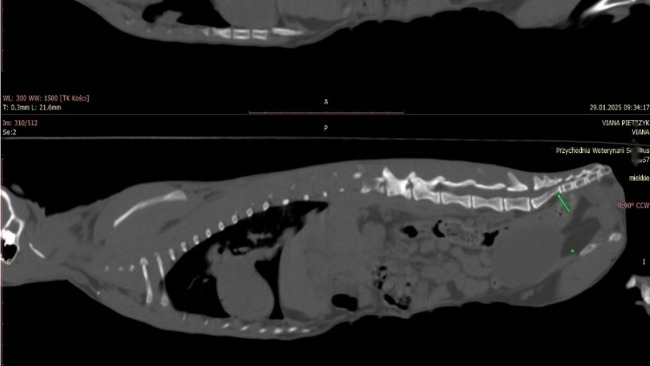

Straciła wtedy ogonek, który musiano amputować. Cała pupa była rozdarta, odbyt trzeba było rekonstruować. Urazowi uległa także miednica, oraz kręgosłup, co wyszło dopiero kilka miesięcy później. W styczniu tego roku Vaiana przestała chodzić i zaczęła załatwiać się pod siebie.